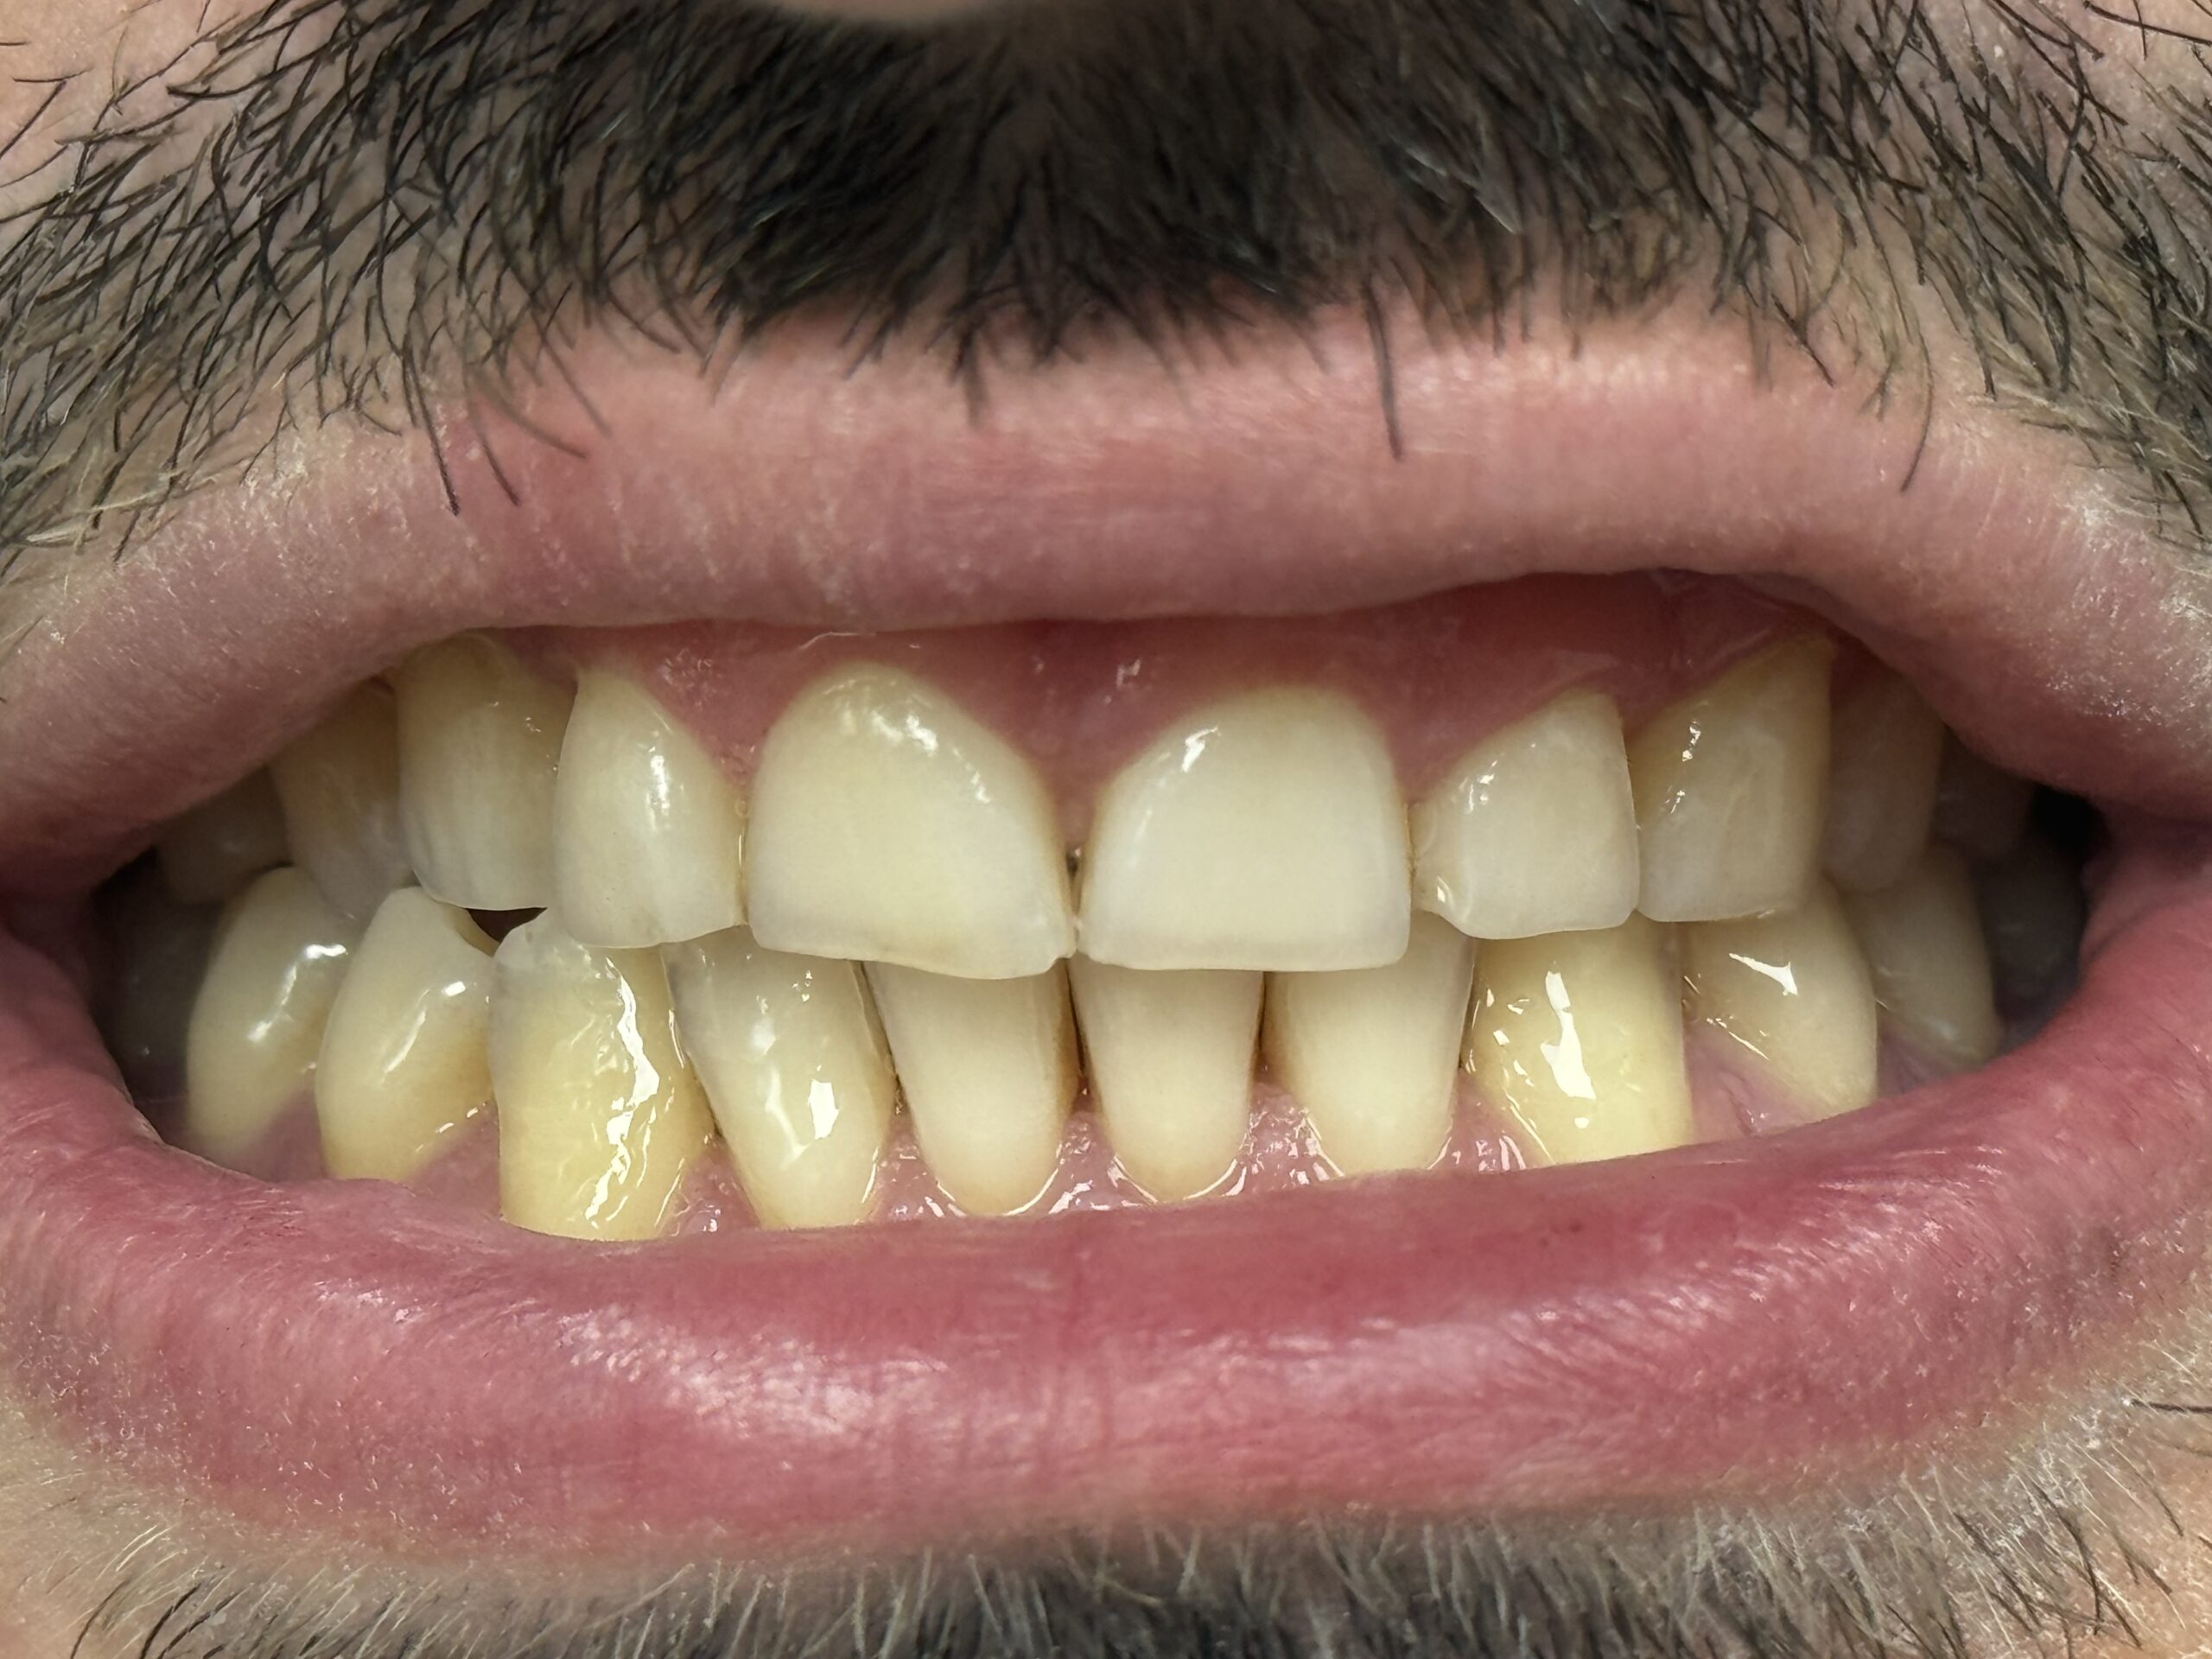

Parodontoza este denumită popular “boala dinților sănătoși”, deoarece această afecțiune distruge în timp țesuturile de susținere ale dinților fără a avea neapărat o simptomatologie precum durere sau carii.

Parodontoza debutează adesea cu gingii roșii, umflate și care sângerează ușor la periaj sau folosirea aței dentare. Pe măsură ce boala progresează, pot apărea retracții gingivale, mobilitate dentară și respirație urât mirositoare. Dacă observi aceste semne, este esențial să consulți un specialist pentru un diagnostic și tratament adecvat.